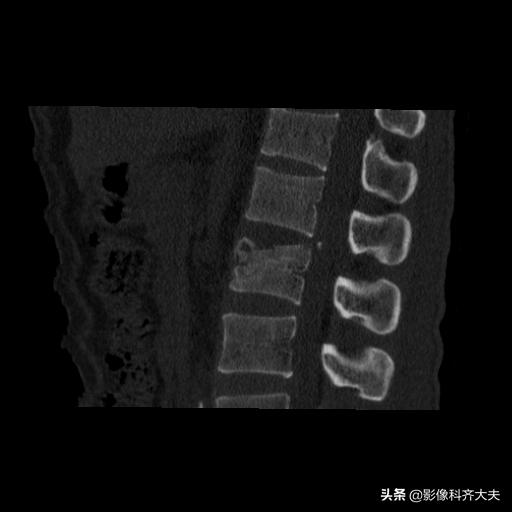

腰二横突骨折

冠状面重建